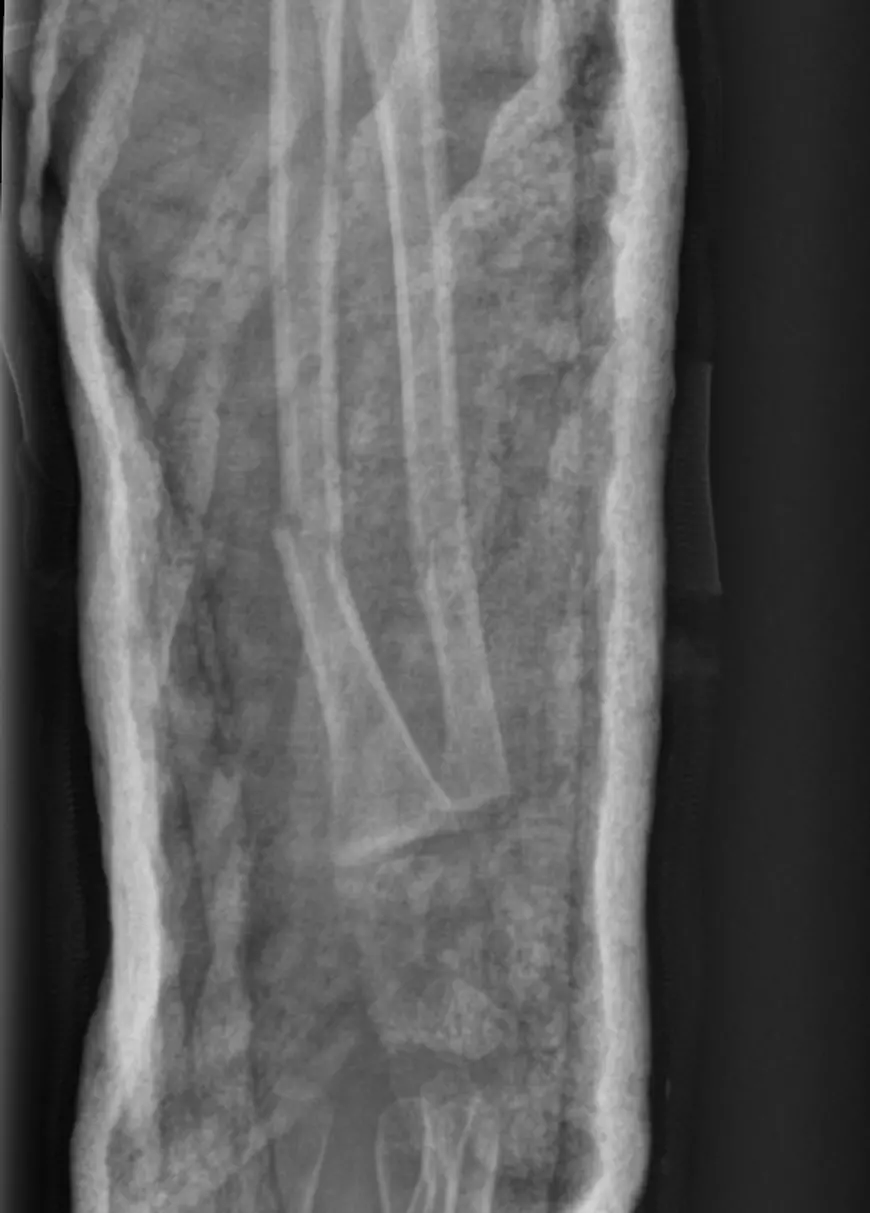

În radiografia pe care doctorul o văzuse, oasele antebrațului subțire al fetiței, învelit în umbra ghipsului, apar strâmbe. Un fapt pe care părinții îl vor afla abia 3 săptămâni mai târziu.

Inițial, văzând radiografiile primite pe WhatsApp, medicul le-a spus că „nu sunt așezate oasele cum trebuie, trebuie intervenție chirurgicală, trebuie refracturată mâna și pusă tijă de metal”.

Doar că medicul Dobrescu nu a menționat un interval de o săptămână. Ci vorbise de trei. Și, mai mult, nu le spusese nimic despre problema vizibilă pe radiografie. Nici nu le-a transmis că o opțiune pentru alinierea oaselor ar fi o intervenție chirurgicală.

Așa că soluția a rămas revenirea periodică la control. Ultima radiografie, efectuată în urmă cu o săptămână, surprinde aceeași angulație în antebrațul fetiței cu care a plecat din Spitalul de Copii din Cluj-Napoca.